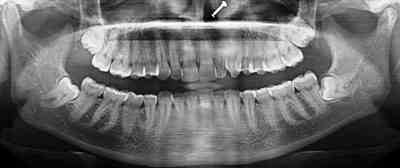

Case 1: A 40-year-old female patient reported to the department of dentistry, with the chief complaint of pain during mastication in the left preauricular region. There was a history of fall from bike one week before. There was no pain or swelling present initially, but she developed pain after one week of trauma which subsided by medication. No history of ear bleed was reported. On palpation, head of the condyle was present in the glenoid fossa, with diminished movements on the left side. In the OPG no fracture was visible. The initial diagnosis of traumatic arthritis was made, and the patient has advised a soft diet and moist heat application. Though the intensity of pain reduced after 2 weeks,it persisted,hence theC.T scan was advised. Computed tomography revealed bony changes in the fractured mandibular condyle and its position in the mandibular fossa more precisely than conventional radiographic examinations. In the axial section, there was a sagittal fracture of the left condyle. Intermaxillary fixation was done for two weeks.

Figure 1. Axial CT showing vertical fracture of left condyle of mandible.